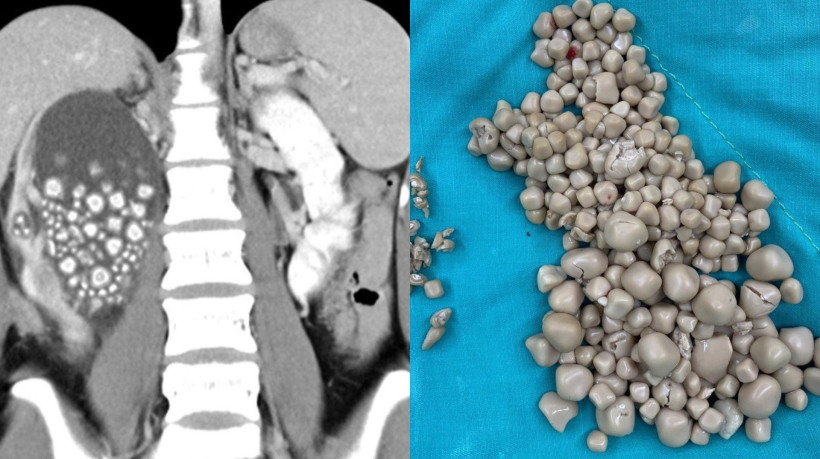

Uma jovem de 20 anos identificada como Xiao Yu teve de se submeter a um procedimento médico para realizar a remoção de mais de 300 pedras acumuladas em seu rim direito. Segundo o jornal local ET Today, Xiao deu entrada no Chi Mei Hospital, na cidade de Tainan, na sexta-feira, 8, alegando febre e dores na região da cintura.

A mulher foi submetida a uma radiografia que revelou inchaço em seus rins além da presença de centenas de pedras alojadas no órgão. Os médicos prescreveram antibióticos e realizaram uma pequena intervenção para remover as pedras. Mais de 300 pedras foram retiradas com medidas entre 0,5 até 2 centímetros de diâmetro.

O cirurgião-chefe Lin Caiyang classificou as pedras como semelhantes a pequenos pães cozidos no vapor. Quando questionada sobre hábitos alimentares, que poderiam acarretar formação de cálculos renais, a jovem alegou não beber água há anos, substituindo o líquido por chás, sucos e bebidas alcoólicas.

A troca resultou em desidratação e na formação de pedras. Além disso, Caiyang ainda ressaltou fatores genéticos como facilitadores para o surgimento de pedras no rim. Xiao recebeu alta dias após o procedimento médico.